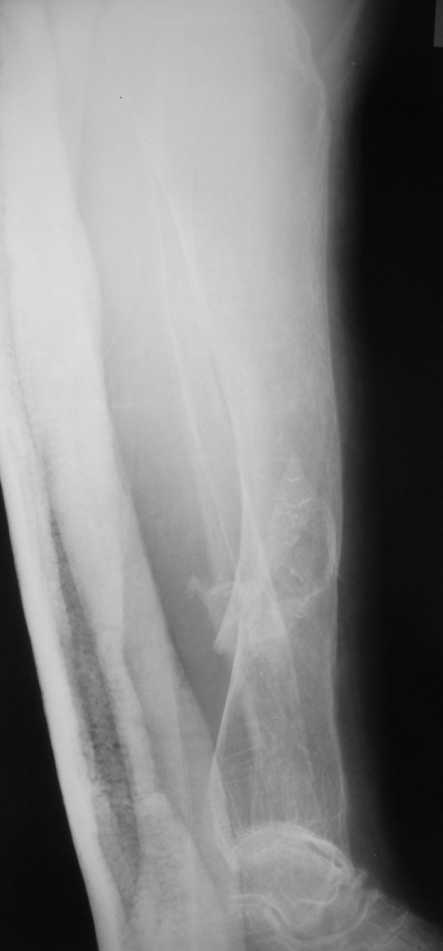

Re: Множественные переломы нижних коенечностей на фоне деформаций

Но даже при малоинвазивной методике лечения применимой для даной больной существуют следующие проблемы: выраженный остеопороз, тонкий кортикал, очень широкий канал.

Контрольные рентгенограммы прилагаю.